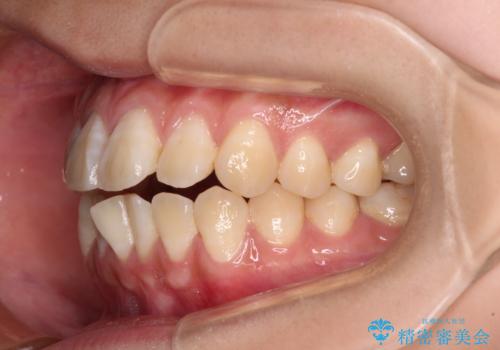

舌の突出癖による開咬と前歯の突出 インビザライン矯正治療

- 上下前歯の非接触と叢生を気にして来院された患者様です。

開咬の改善はインビザラインの最も得意とするところであるため、インビザラインを用いて矯正治療を行うこととしました。

治療開始直後に上顎前歯に激しい痛みが発現し、矯正治療を休んだり、マウスピースの装着時間を短くしたりと工夫をしましたが、残念ながら治療途中で失活していることが分かりました。

矯正治療の途中で前歯の根管治療とオールセラミッククラウンによる補綴治療を行い、その後インビザライン1セットを用いて細かい部分を仕上げました。